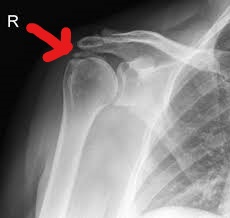

Calcific Tendonitis Can Mimic Septic Arthritis! Gepost op 31 januari 2019 door netwerkvsseh Advanced Practice – Calcific Tendonitis Can Mimic Septic Arthritis! @emdaily.cooperhealth.org Dit delen: Delen op X (Opent in een nieuw venster) X Share op Facebook (Opent in een nieuw venster) Facebook Delen op LinkedIn (Opent in een nieuw venster) LinkedIn E-mail een link naar een vriend (Opent in een nieuw venster) E-mail Afdrukken (Opent in een nieuw venster) Print Vind-ik-leuk Aan het laden... Gerelateerd